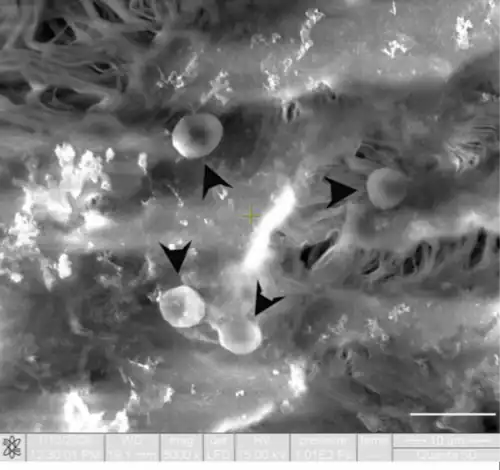

Un rasgo llamativo de las células endoteliales es la presencia de una numerosa población de vesículas del plasmalema de unos 70 nanómetros (nm) de diámetro, de cuello delgado, que están presentes en ambas superficies celulares y que se abren a la luz y al espacio extravascular.

En la superficie extraluminal o externa, las células endoteliales están en contacto con la membrana basal y sustancias como colágeno, proteglicanos, heparánsulfato, integrinas; en la parte luminal las células endoteliales en contacto con la sangre poseen mucopolisacáridos, glucoproteínas, fibrinógeno y algo de fibrina.